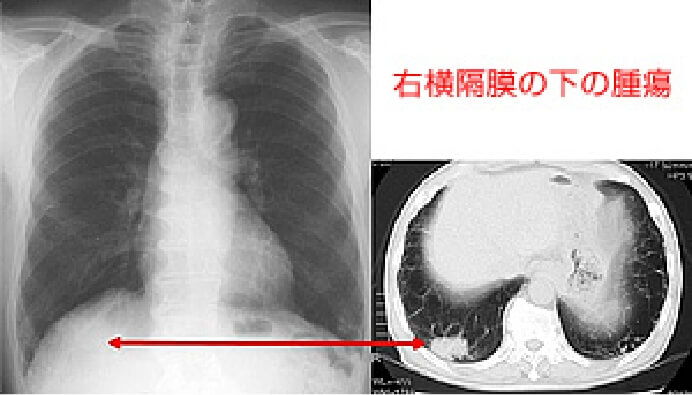

おもに呼吸器(気管・肺など)、循環器(心臓)などに病気があるかどうかを調べるための検査です。肺がん・じん肺・肺結核・肺炎・気胸・胸水・心拡大などの診断に有用です。しかし、小さな肺がんは検出されないことがあるため(症例画像参照)、喀痰細胞診検査・胸部CT検査をあわせておこないます。

肺・気管・気管支などを輪切り(断面)の状態で撮影し、小さい病変を見つける検査です。早期肺がんの診断はもちろんのこと、「低線量CT装置」を用いることにより、X線写真では発見しにくい中心型(肺門型)肺がんも検出することができます。(症例画像参照)

単純X線写真で発見困難な症例3